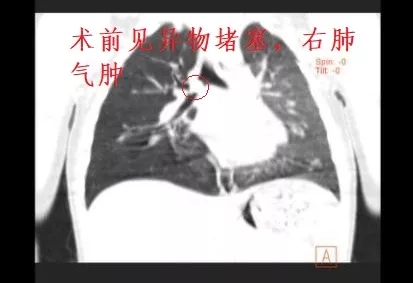

术前CT检查

据悉,啵啵(化名)在家中一边吃玉米一边与姐姐打闹,突然出现呛咳、面色紫绀,家属立即送至当地医院就诊,当地医院缺乏医疗设备,立即转送至河池市人民医院救治。急诊行CT检查提示“右主支气管异物并右肺气肿”,急诊科立即将患儿送至儿内科住院治疗,当班医师接诊患儿后立即请示韦瑞含副主任,韦瑞含副主任认为患儿年龄小,气管较狭窄,需与内镜中心协作取出异物。儿内科立即联系呼吸与危重症医学科韦庆主任,韦庆主任了解病情后,指出患儿异物堵塞气管严重,已出现肺气肿,需尽快将异物取出,当即拟定手术方案,决定为患儿行支气管镜下异物取出术。